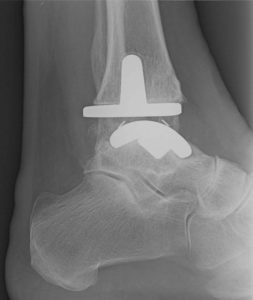

Prótesis de tobillo

La prótesis de tobillo es una técnica quirúrgica de muy buenos resultados y que sirve como una de las opciones de tratamiento para la atrosis de tobillo. Otra forma de tratamiento de la artrosis de tobillo son la artrodesis o fijación del tobillo.

La prótesis de tobillo consiste en dos componentes metálicos y un componente de polietileno que reemplazan la movilidad de la articulación del tobillo. La cirugía de prótesis de tobillo es relativamente corta, con una duración aproximada de una hora y puede estar asociada a procedimientos en tendones (transferencias tendíneas) o procedimientos sobre huesos como las osteotomías.